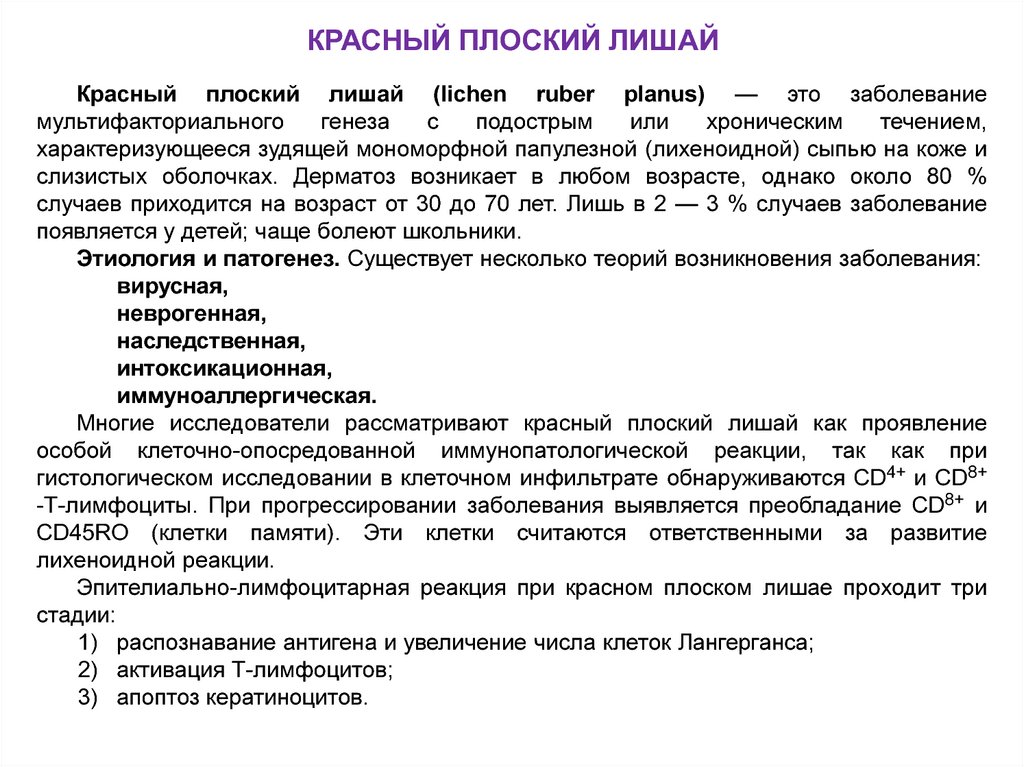

Фото Красного Плоского

Фото Красного Плоского 103 фото